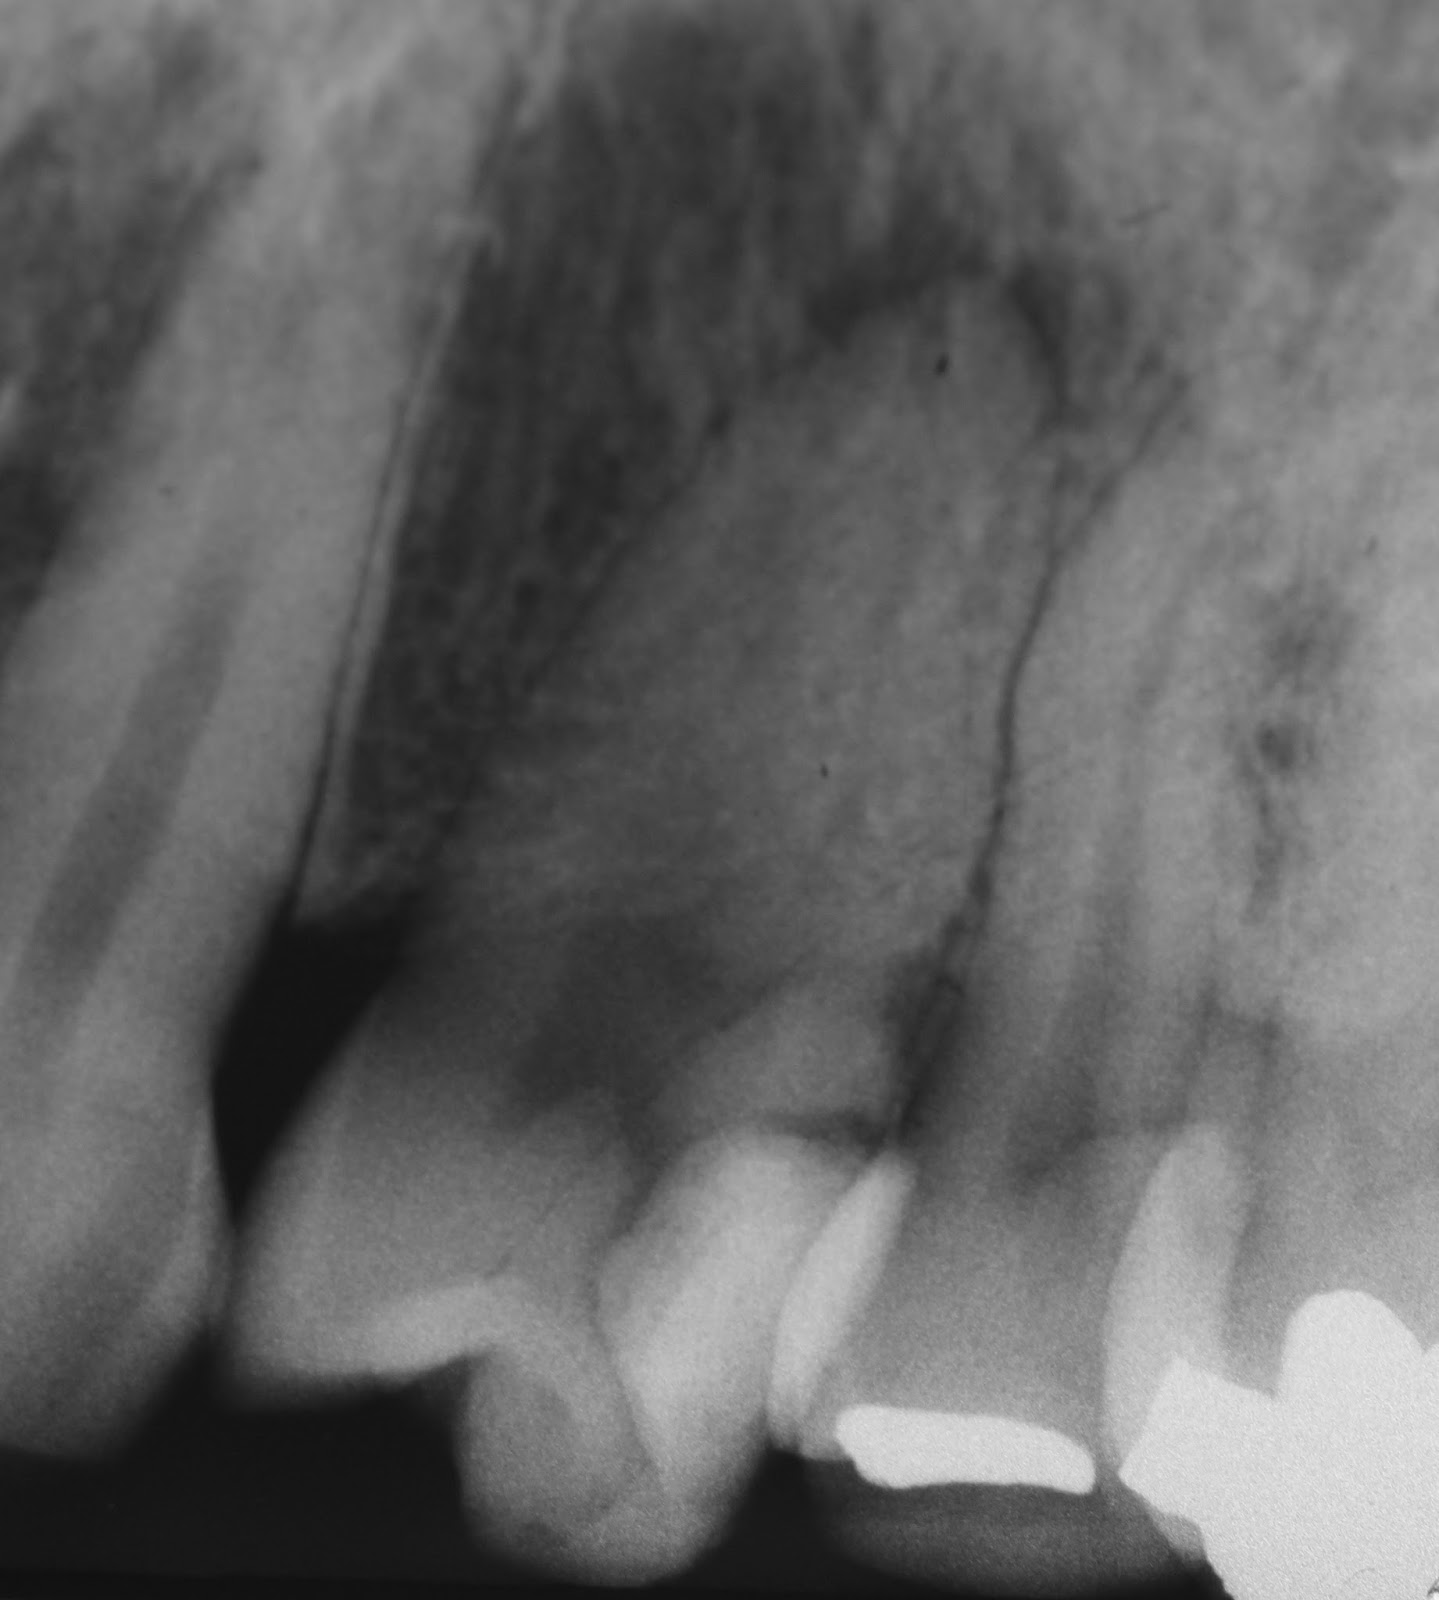

Figure 1 from Comparison of Obturation Quality in Modified Continuous

Figure 1 from Comparison of Obturation Quality in Modified Continuous Warm Vertical Technique  Web  the warm vertical technique has shown greater ability to flow into canal irregularities than the cold lateral technique. Web  the technique used in warm vertical compaction may make it possible for accessory apical anatomy and internal. Web warm vertical obturation is a technique favored by many endodontists and general dentists. Web  warm vertical condensation technique still the most efficient. Warm Vertical Technique.